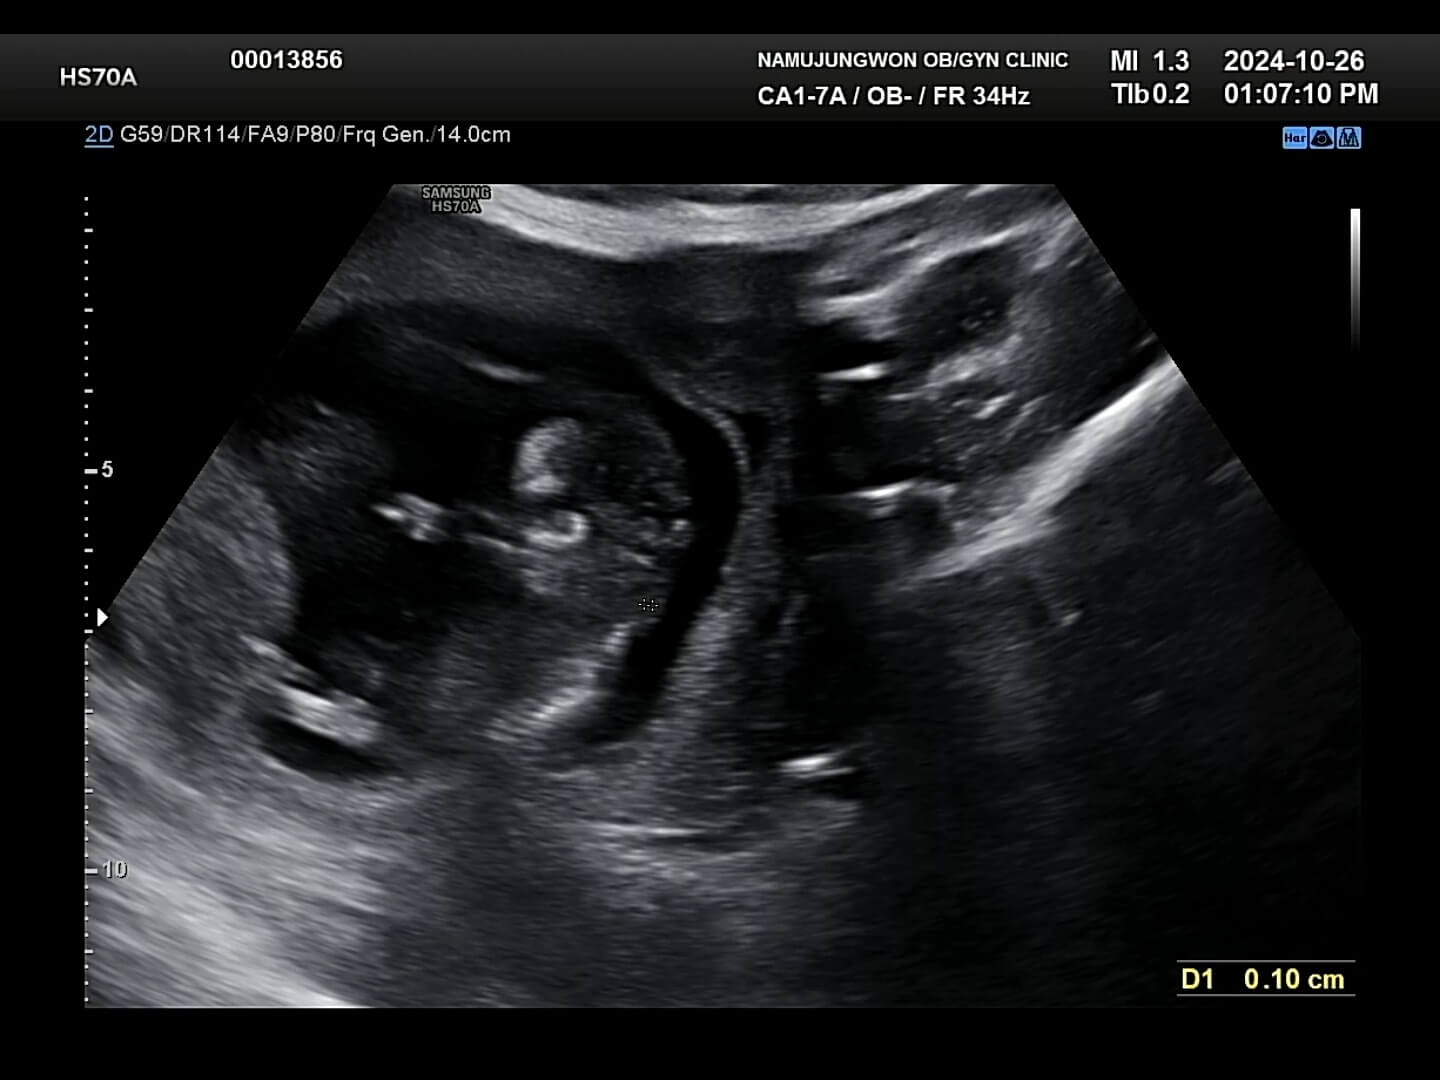

4. 12주 입체초음파

드디어 12주가 되어 꾸미의 첫 입체초음파를 보는 날이 되었어요! 두근두근, 꾸미는 얼마나 커있을까요?

12주-입체초음파 12주에는 첫 입체초음파를 보게 되면서 팔, 다리가 잘 형성되었는지 정도를 보는 것 같아요. 12주부터 '태아'라고 부르기도 한답니다. 우리 꾸미는 처음에는 등을 돌리고 있다가 서서히 얼굴을 보여줬습니다. 벌써부터 귀여워요! 아들인지 딸인지 너무 궁금했는데요, 성별은 입체 초음파가 아닌 일반 초음파로 봐야한다고 하셨어요.